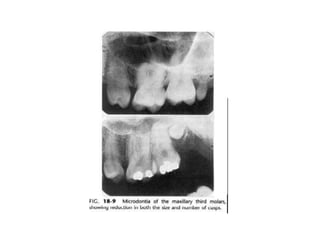

4. Microdontia

Merupakan gigi yang ukurannya lebih kecil

daripada ukuran normal.